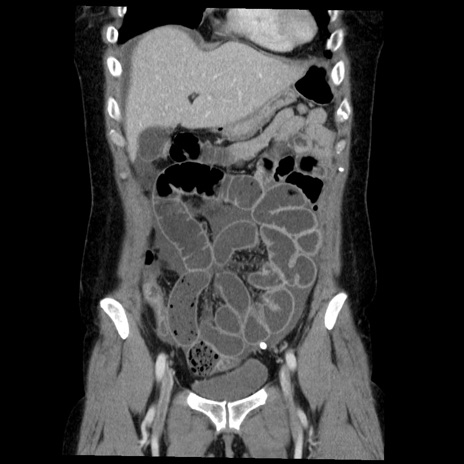

横断像

症例6(冠状断像)

【症例】50歳代女性

【主訴】下腹部痛

【現病歴】本日朝より下痢2回あり。 昼食を食べた後、嘔吐3回、下腹部痛認め、症状軽快せず、当院救急搬送。

最終食事:本日昼(生ものなし)。 昨日の夜、刺身を食ぺたとのこと。周囲に同様の症状の者なし。普段、排便は毎日あるとのこと。

【既往歴】卵巣癌術後(8年前に当院で卵巣摘出)

【身体所見】 意識清明、腹部:平坦、腸蠕動音→、やや硬、下腹部自発痛・圧痛あり、反跳痛あり、筋性防御なし。

【データ】WBC 16000、CRP 0.01